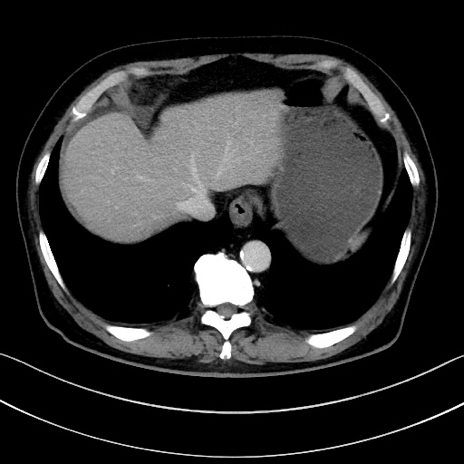

症例15(横断像)

【症例】70歳代男性

【主訴】腹痛

【現病歴】今朝から腹痛あり。全体的に痛い。特に左上の方。排ガスが今日はない。冷や汗が出る。

【既往歴】直腸癌術後

【身体所見】左側腹部〜上腹部に圧痛あり。腹膜刺激症状明らかなではない。軽度反跳痛。左下腹部に術後瘢痕あり。

【データ】WBC 7700、CRP 0.02